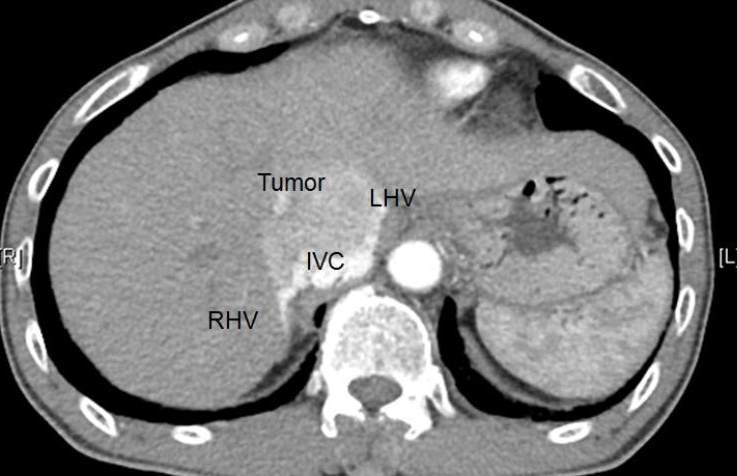

neoplastic obstruction

IVC flow obstruction caused by primary tumors that typically propagate from hepatic or renal veins

rare

extrinsic tumors can also cause compression or invasion into IVC (abdo tumors along midline)

sono feats:

visualization of intraluminal tumor

tumor will demonstrate blood flow within, thrombus wont

visualization of extrinsic tumor mass that compresses & obstructs IVC

variable echogenicity

dilation of IVC and tributary veins below lvl of obstruction

continuous flow below the point of obstruction